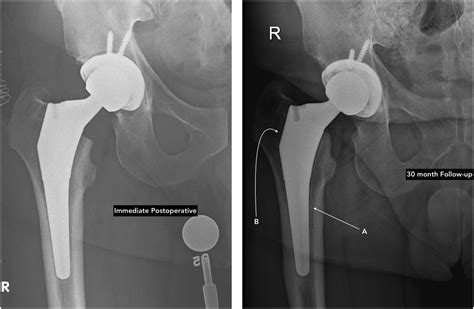

Gathering this information helps your doctor understand the functional impact the pain has on your life. Be prepared to discuss your medical history, any past injuries, and previous attempts at conservative treatment. Your surgeon will typically order X-rays to visualize the joint space and assess the degree of bone-on-bone contact or deformity.

Modern surgical techniques have significantly advanced, making hip replacement one of the most successful orthopedic procedures. While the idea of surgery can be daunting, the primary goal of the procedure is to relieve pain and improve your ability to function. After surgery, patients typically begin physical therapy almost immediately, focusing on strengthening the muscles around the new joint to support long-term stability and mobility.